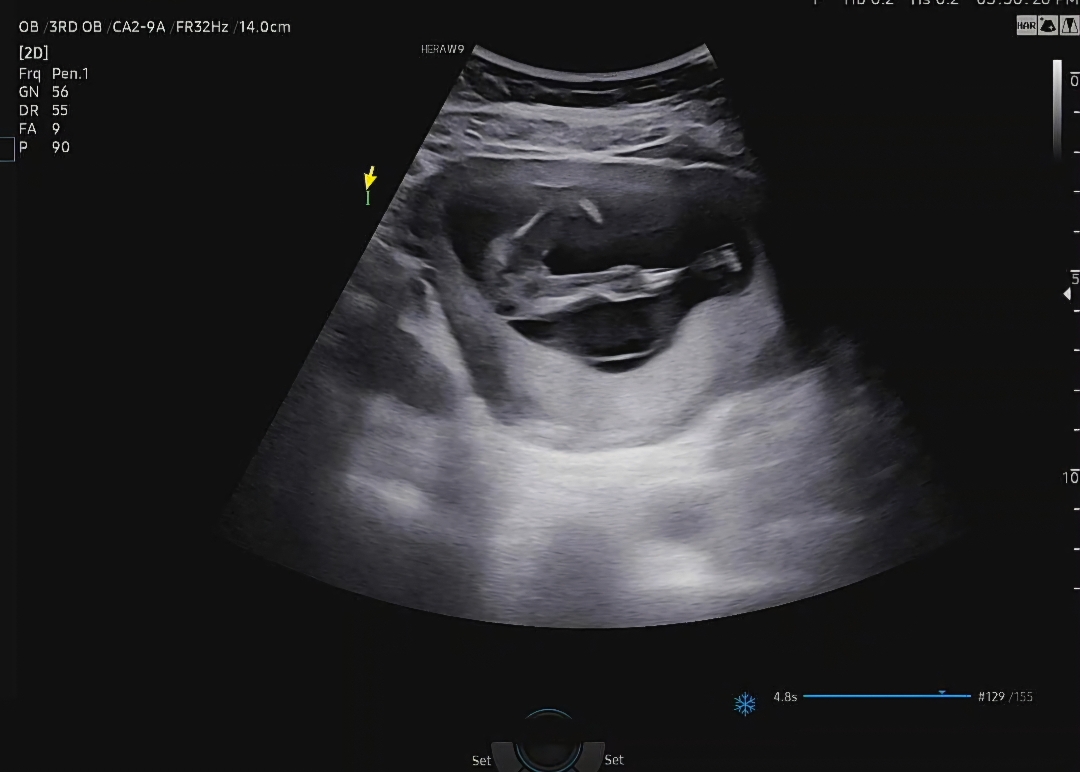

15주 성별봐주세요!!😆

15주 초음파 보고왔는데 성별은 안알려주셨어요!! 혹시 성별예측할수 있을까요??!

이거만 보면 딸같은데용~